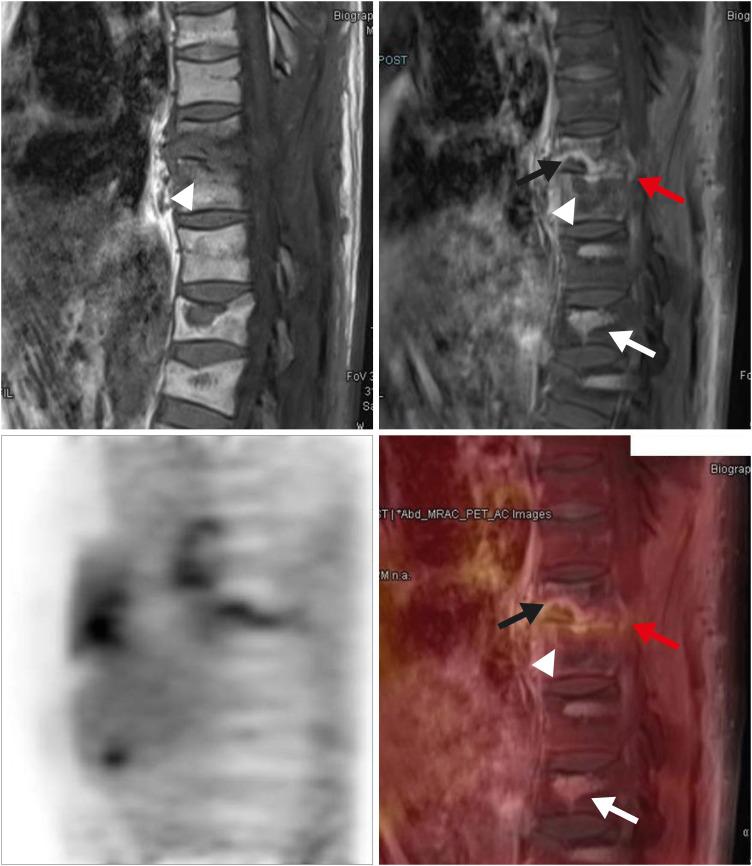

Magnetic resonance imaging (MRI) is the preferred imaging method for evaluating treatment response in spine infection. However, there are still no definite correlation between follow-up MRI findings and clinical status. Recently, Fluorine-18 fluorodeoxyglucose positron emission tomography (18F-FDG PET) shows great potential as diagnostic and monitoring options. Simultaneous 18F-FDG PET/MRI makes us to expect a huge synergic effect on diagnosis and evaluation of treatment response with metabolic and anatomical advantages in spine infection. We introduce an application of 18F-FDG PET/MRI for evaluating residual lesion in the patient with pyogenic spine infection.

磁共振成像(MRI)是评估脊柱感染治疗反应的首选成像方法。然而,随访MRI表现与临床状况之间仍无明确的相关性。最近,氟-18氟脱氧葡萄糖正电子发射断层扫描(18F-FDG PET)作为诊断和监测手段显示出巨大潜力。同时进行的18F-FDG PET/MRI使我们期望在脊柱感染的诊断和治疗反应评估方面产生巨大的协同效应,兼具代谢和解剖学优势。我们介绍了18F-FDG PET/MRI在评估化脓性脊柱感染患者残余病变中的应用。